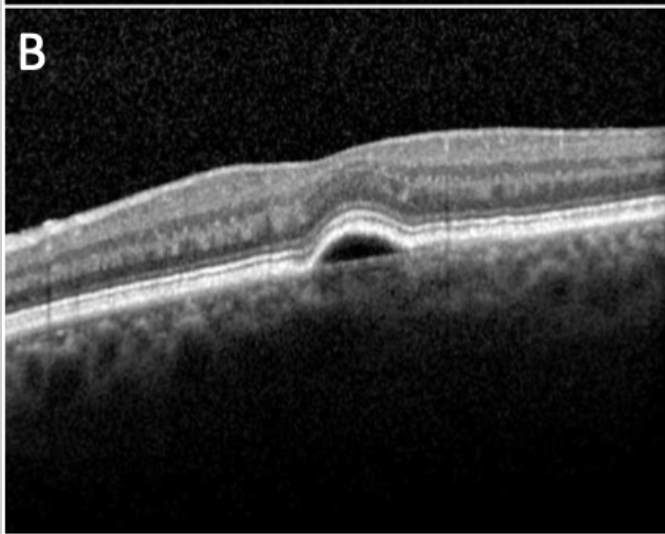

Which classification of CNVM is this?

Type 2 ("classic") new vessels pass through the RPE thus is located above the RPE in the subretinal space.